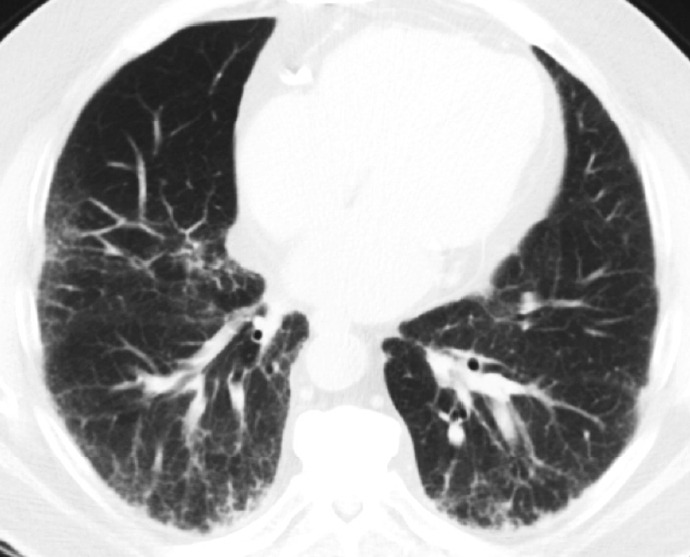

Histopathologic criteria of usual interstitial pneumonia (UIP)/idiopathic pulmonary fibrosis (IPF) were defined over the years and endorsed by leading organizations decades after Dr. Averill A. Liebow first coined the term UIP in the 1960s as a distinct pathologic pattern of fibrotic interstitial lung disease. Novel technology and recent research on interstitial lung diseases with genetic component shed light on molecular pathogenesis of UIP/IPF. Two antifibrotic agents introduced in the mid-2010s opened a new era of therapeutic approaches to UIP/IPF, albeit contentious issues regarding their efficacy, side effects, and costs. Recently, the concept of progressive pulmonary fibrosis was introduced to acknowledge additional types of progressive fibrosing interstitial lung diseases with the clinical and pathologic phenotypes comparable to those of UIP/IPF. Likewise, some authors have proposed a paradigm shift by considering UIP as a stand-alone diagnostic entity to encompass other fibrosing interstitial lung diseases that manifest a relentless progression as in IPF. These trends signal a pendulum moving toward the tendency of lumping diagnoses, which poses a risk of obscuring potentially important information crucial to both clinical and research purposes. Recent advances in whole slide imaging for digital pathology and artificial intelligence technology could offer an unprecedented opportunity to enhance histopathologic evaluation of interstitial lung diseases. However, current clinical practice trends of moving away from surgical lung biopsies in interstitial lung disease patients may become a limiting factor in this endeavor as it would be difficult to build a large histopathologic database with correlative clinical data required for artificial intelligence models.